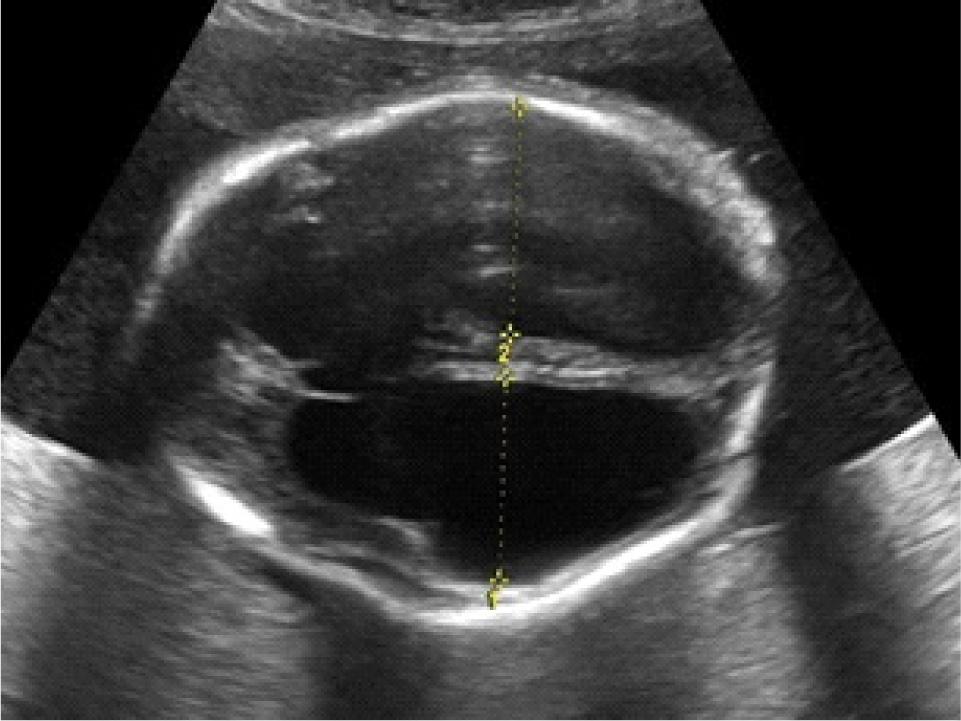

Ultrasonography at 31+1 weeks of gestation revealed severe bilateral ventriculomegaly with areas of hyperechogenicities in the periventricular region (Figure 1), cardiomegaly, hepatosplenomegaly with intrahepatic hyperechogenicites (Figure 2), and polyhydramnios. Fetal congenital infection was suspected and fetal blood sampling was performed and sent for serologic testing. The result was positive for T. gondii IgG and IgM antibodies.

Figure 1

Ultrasound image. Transventricular view of the fetal head shows severe dilatation of lateral ventricles with thinning of the cerebral cortex and periventricular calcification. The lateral ventricle measures 35.9 mm.